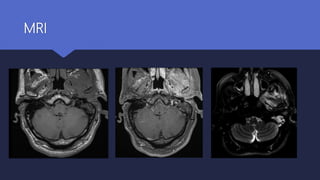

 MRI scan

Useful for assessing the initial severity of the disease

Excellent at delineating the extent of soft tissue disease

Intracranial complications

MRI

Diagnosis Radiological investigations  Ctscan : Defines the anatomical extent of the disease Remains the initial investigation of choice  MRI scan Useful for assessing the initial severity of the disease Excellent at delineating the extent of soft tissue disease Intracranial complications

• #20 MRI of same patient: axial T1WI (A), post contrast (B) and fat saturated T2WI (C) demonstrates extensive inflammation and enhancement of the left EAC, periauricular region, masticator, parotid and parapharyngeal spaces. These areas are hyperintense on T2WI. Note mastoid airspace disease. This can be mistaken for an aggressive tumor.